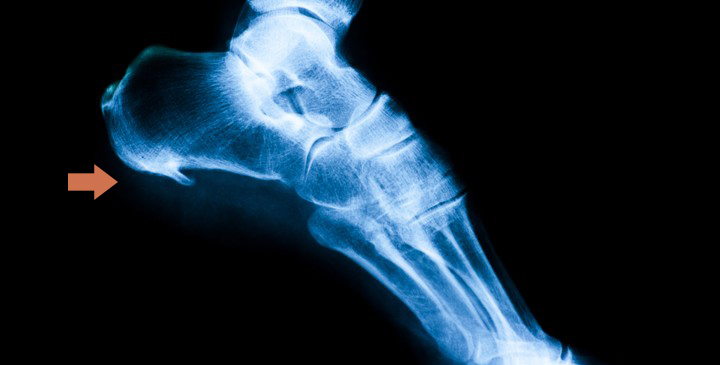

El espolón calcáneo es un crecimiento del hueso del talón en forma triangular o de lanza. Se produce cuando la fascia plantar (tejido elástico que une el talón con la zona de debajo de los dedos del pie) está sometida a excesiva tracción y sobrecarga generando unas microrroturas en su inserción. Esta parte se calcifica formándose esa especie de “hueso” que provoca un dolor agudo en el talón, como si fuesen pinchazos.

Tras ello, se procede al examen clínico, que suele ser suficiente para detectar esta patología. Lo aconsejable es realizar una prueba radiológica en la que se observará si existe esa calcificación que tendrá forma de “saliente puntiagudo” que sale desde el talón hacia el interior del pie. Si en esta prueba no aparece esta nueva formación, hablaremos de fascitis plantar.